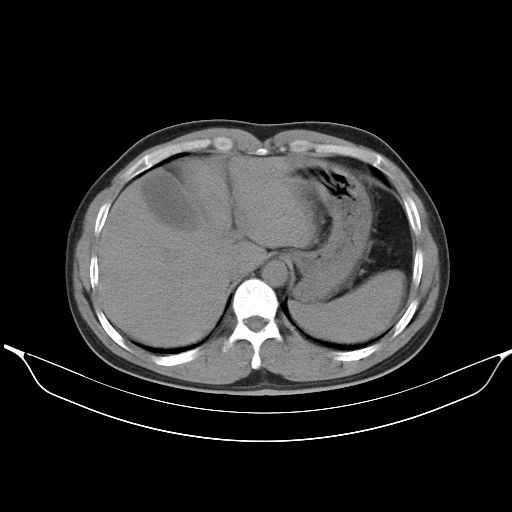

标题: CT25490:男,40岁,体检发现;无其它不适。 [打印本页]

标题: CT25490:男,40岁,体检发现;无其它不适。

2、轻度脂肪肝。

考虑右下肺周围性肺癌并肺内多发转移,纵隔淋巴结转移!

支持 !考虑右下肺周围性肺癌并肺内多发转移,纵隔淋巴结转移,(气管前腔静脉后,隆突下,主动脉弓下都有了)